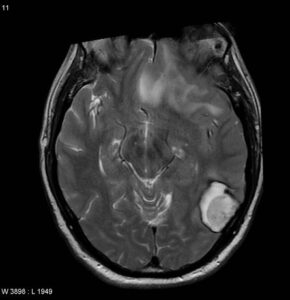

Formazioni metastatiche cerebrali